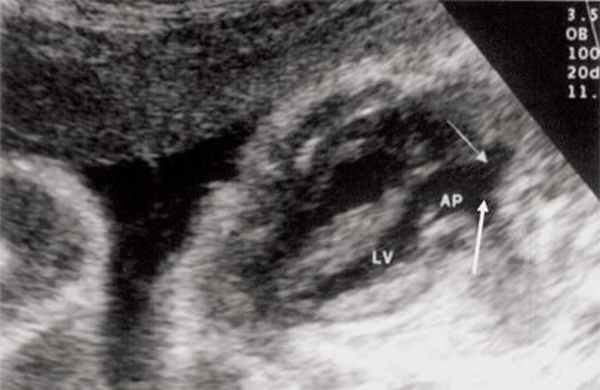

Рис. 9. Синдром Тауссиг - Бинга. Легочная артерия (отмечена стрелкой) расположена над дефектом межжелудочковой перегородки.